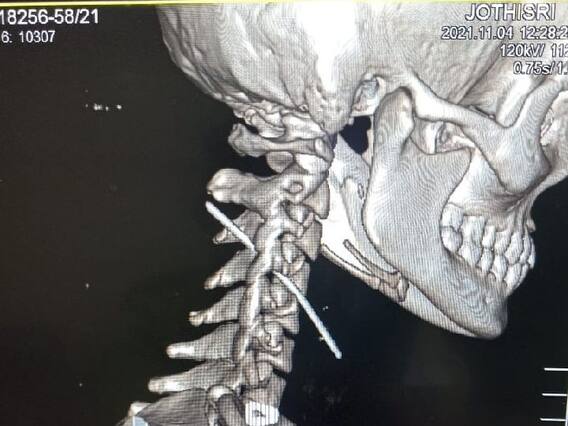

கோவை, தியாகராய நகர் பகுதியைச் சேர்ந்த 19 வயது இளம்பெண் ஒருவர், கழுத்தை அறுத்து கொண்டு தற்கொலைக்கு முயன்றுள்ளார். இதை அடுத்து கழுத்து அறுபட்ட நிலையில் கடந்த 2ஆம் தேதி கோவை அரசு மருத்துவ கல்லூரி மருத்துவமனையில் சிகிச்சைக்காக அனுமதிக்கப்பட்டார். அவரை பரிசோதித்த மருத்துவர்கள் கழுத்தில் வெளிப்புற காயங்கள் இருந்ததால் முதலுதவி செய்தனர். எனினும் கழுத்தில் ஏற்பட்ட காயம் குணமான பின்னரும், அவருக்கு கழுத்து வலி இருந்துள்ளது. இதனை அடுத்து அப்பெண்ணிற்கு சிடி ஸ்கேன் பரிசோதனை செய்த போது, 7.5 செ.மீ. அளவுக்கு நீளமான தையல் ஊசி, கழுத்தில் மூச்சு குழாயில் இருந்து கழுத்து தண்டு பகுதியில் மூளைக்கு செல்லும் ரத்தக்குழாய் அருகில் இருப்பது தெரியவந்தது. இது குறித்து மருத்துவர்கள் அவரிடம் கேட்ட போது, தற்கொலை செய்து கொள்ள தான் அந்த ஊசியை கழுத்தில் குத்தியதாக தெரிவித்துள்ளார்.

இதனை அடுத்து மூளைக்கு செல்லும் ரத்த குழாய்க்கு அருகே தையல் ஊசி இருப்பதால் அறுவை சிகிச்சை செய்து ஊசியை எடுப்பது என்பது சவாலாகவும், நோயாளியின் உயிருக்கு ஆபத்து ஏற்பட வாய்ப்பு இருந்தது. தண்டு வட மருத்துவர்கள், ரத்த நாள மருத்துவர்கள், காது, மூக்கு, தொண்டை மருத்துவர்கள், மயக்கவியல் மருத்துவர்கள் கலந்து ஆலோசித்து அறுவை சிகிச்சை செய்ய முடிவெடுத்தனர். இதன்படி கழுத்தில் இருந்து தண்டுவட எலும்பு பகுதியில் அறுவை சிகிச்சை செய்து மூச்சுக் குழாயில் இருந்து தண்டுவடத்தின் வழியாக கழுத்தின் பின்புறம் சென்று கொண்டிருந்த ஊசி கண்டறியப்பட்டது. பின்னர் நவீன சி.ஆர்.எம் எக்ஸ்ரே கருவியின் மூலம் ஊசி இருக்குமிடம் உறுதி செய்யப்பட்டு, அந்த ஊசி மெதுவாக துல்லியமாக வெளியே எடுக்கப்பட்டது.